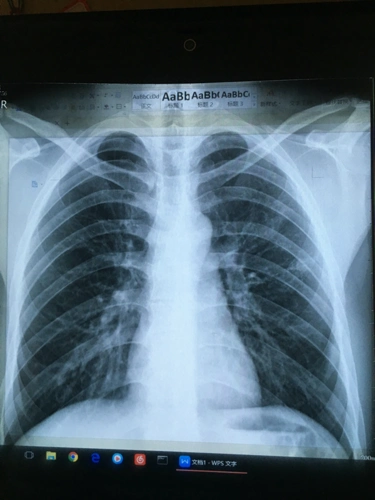

四年前得过肺结核,后治愈,要参加公务员体检了,帮忙看下这张胸片有没